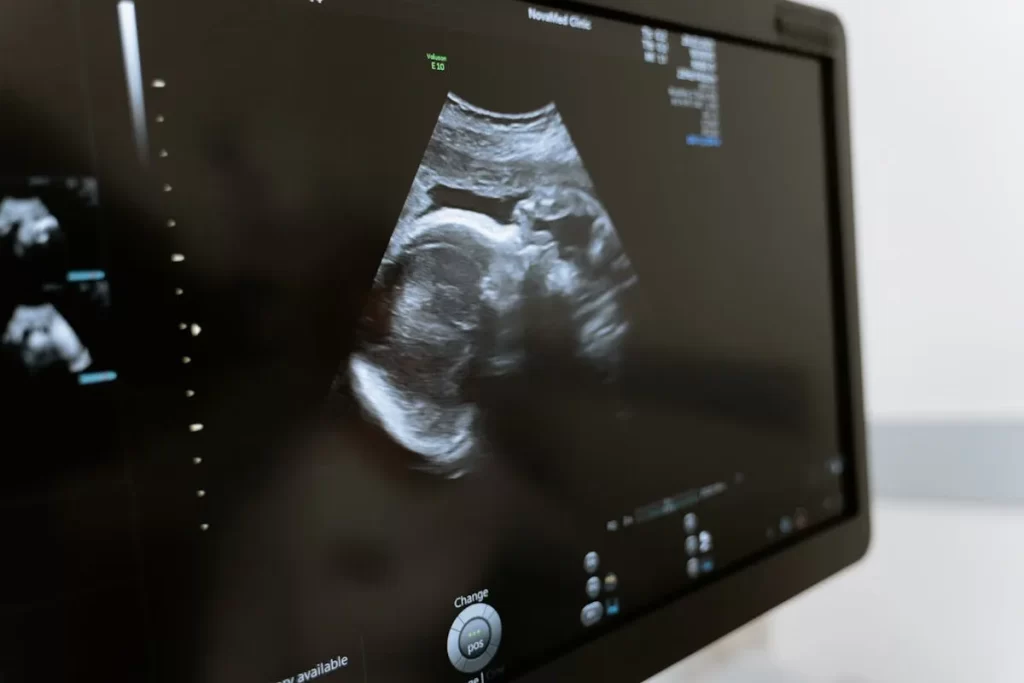

O ultrassom morfológico é um exame detalhado que avalia a formação anatômica e o desenvolvimento do bebê durante a gestação, sendo um dos mais importantes para a saúde materno-fetal.

Ele fornece informações precisas sobre órgãos, ossos, membros e estruturas cerebrais, permitindo identificar precocemente possíveis alterações.

Além de seu valor diagnóstico, o exame também proporciona tranquilidade aos pais ao possibilitar a visualização nítida do bebê ainda dentro do útero.

Realizado com tecnologia de ponta, o ultrassom morfológico utiliza ondas sonoras para formar imagens em tempo real, sem riscos à mãe ou ao feto. Entre os principais benefícios do ultrassom morfológico estão: